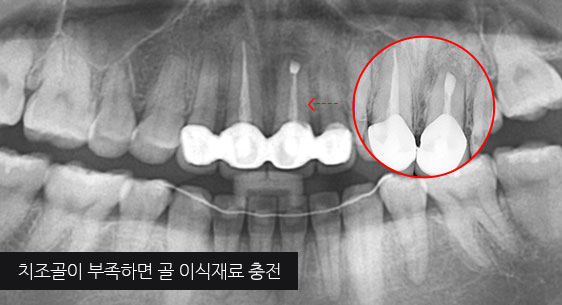

기존 신경치료는 양호한 상태이나 치근부위에 염증과 치조골 소실이 진행 중

치아 뿌리 쪽 잇몸을 절개하고 치조골 부위의 염증조직을 제거.(난이도 중)

심한 염증으로 치조골이 광범위하게 소실, 아래쪽 신경관이 가까이 있어 치근단수술이 불가능한 상태, 타 병원에서 임플란트 진단을 받았지만,

고운미소치과에서 치아를 발치하고 뿌리 쪽 염증을 제거한 후 발치한 치아를 다시 심는 치아재식술을 시행하였습니다.

기존 신경치료 부위에 염증과 치조골이 소실되고 있는 상태

치아를 발치하고 염증을 제거, MTA로 충전하고 치아를 다시 심음. (난이도 중)